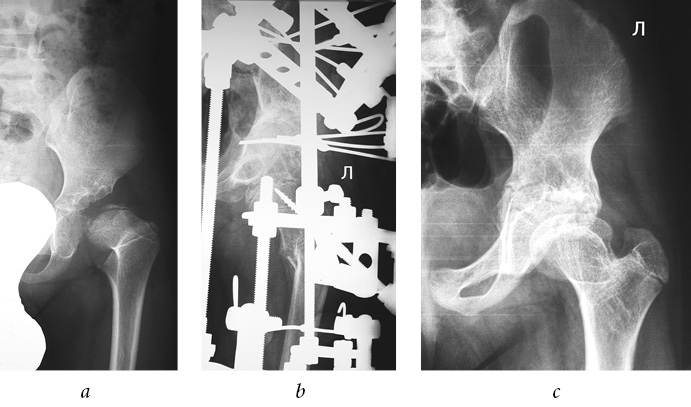

There were no cases among the joints examined that presented with an excellent outcome. Good results were noted only when performing extra-articular interventions (see Table 2). In general, positive outcomes were observed in 94% (Figs. 1–3).

Fig. 2. Patient D., 4 years old, with a diagnosis of subluxation of the left hip, degree II of dislocation, and degree II Perthes disease: a — frontal radiograph of the hip joint before treatment; b — frontal of the hip joint during treatment (after tunneling of the femoral neck and head, extra-articular reconstruction of the pelvic and femoral components of the joint, and hardware decompression of the joint); c — frontal radiograph of the hip joint 3 years after treatment